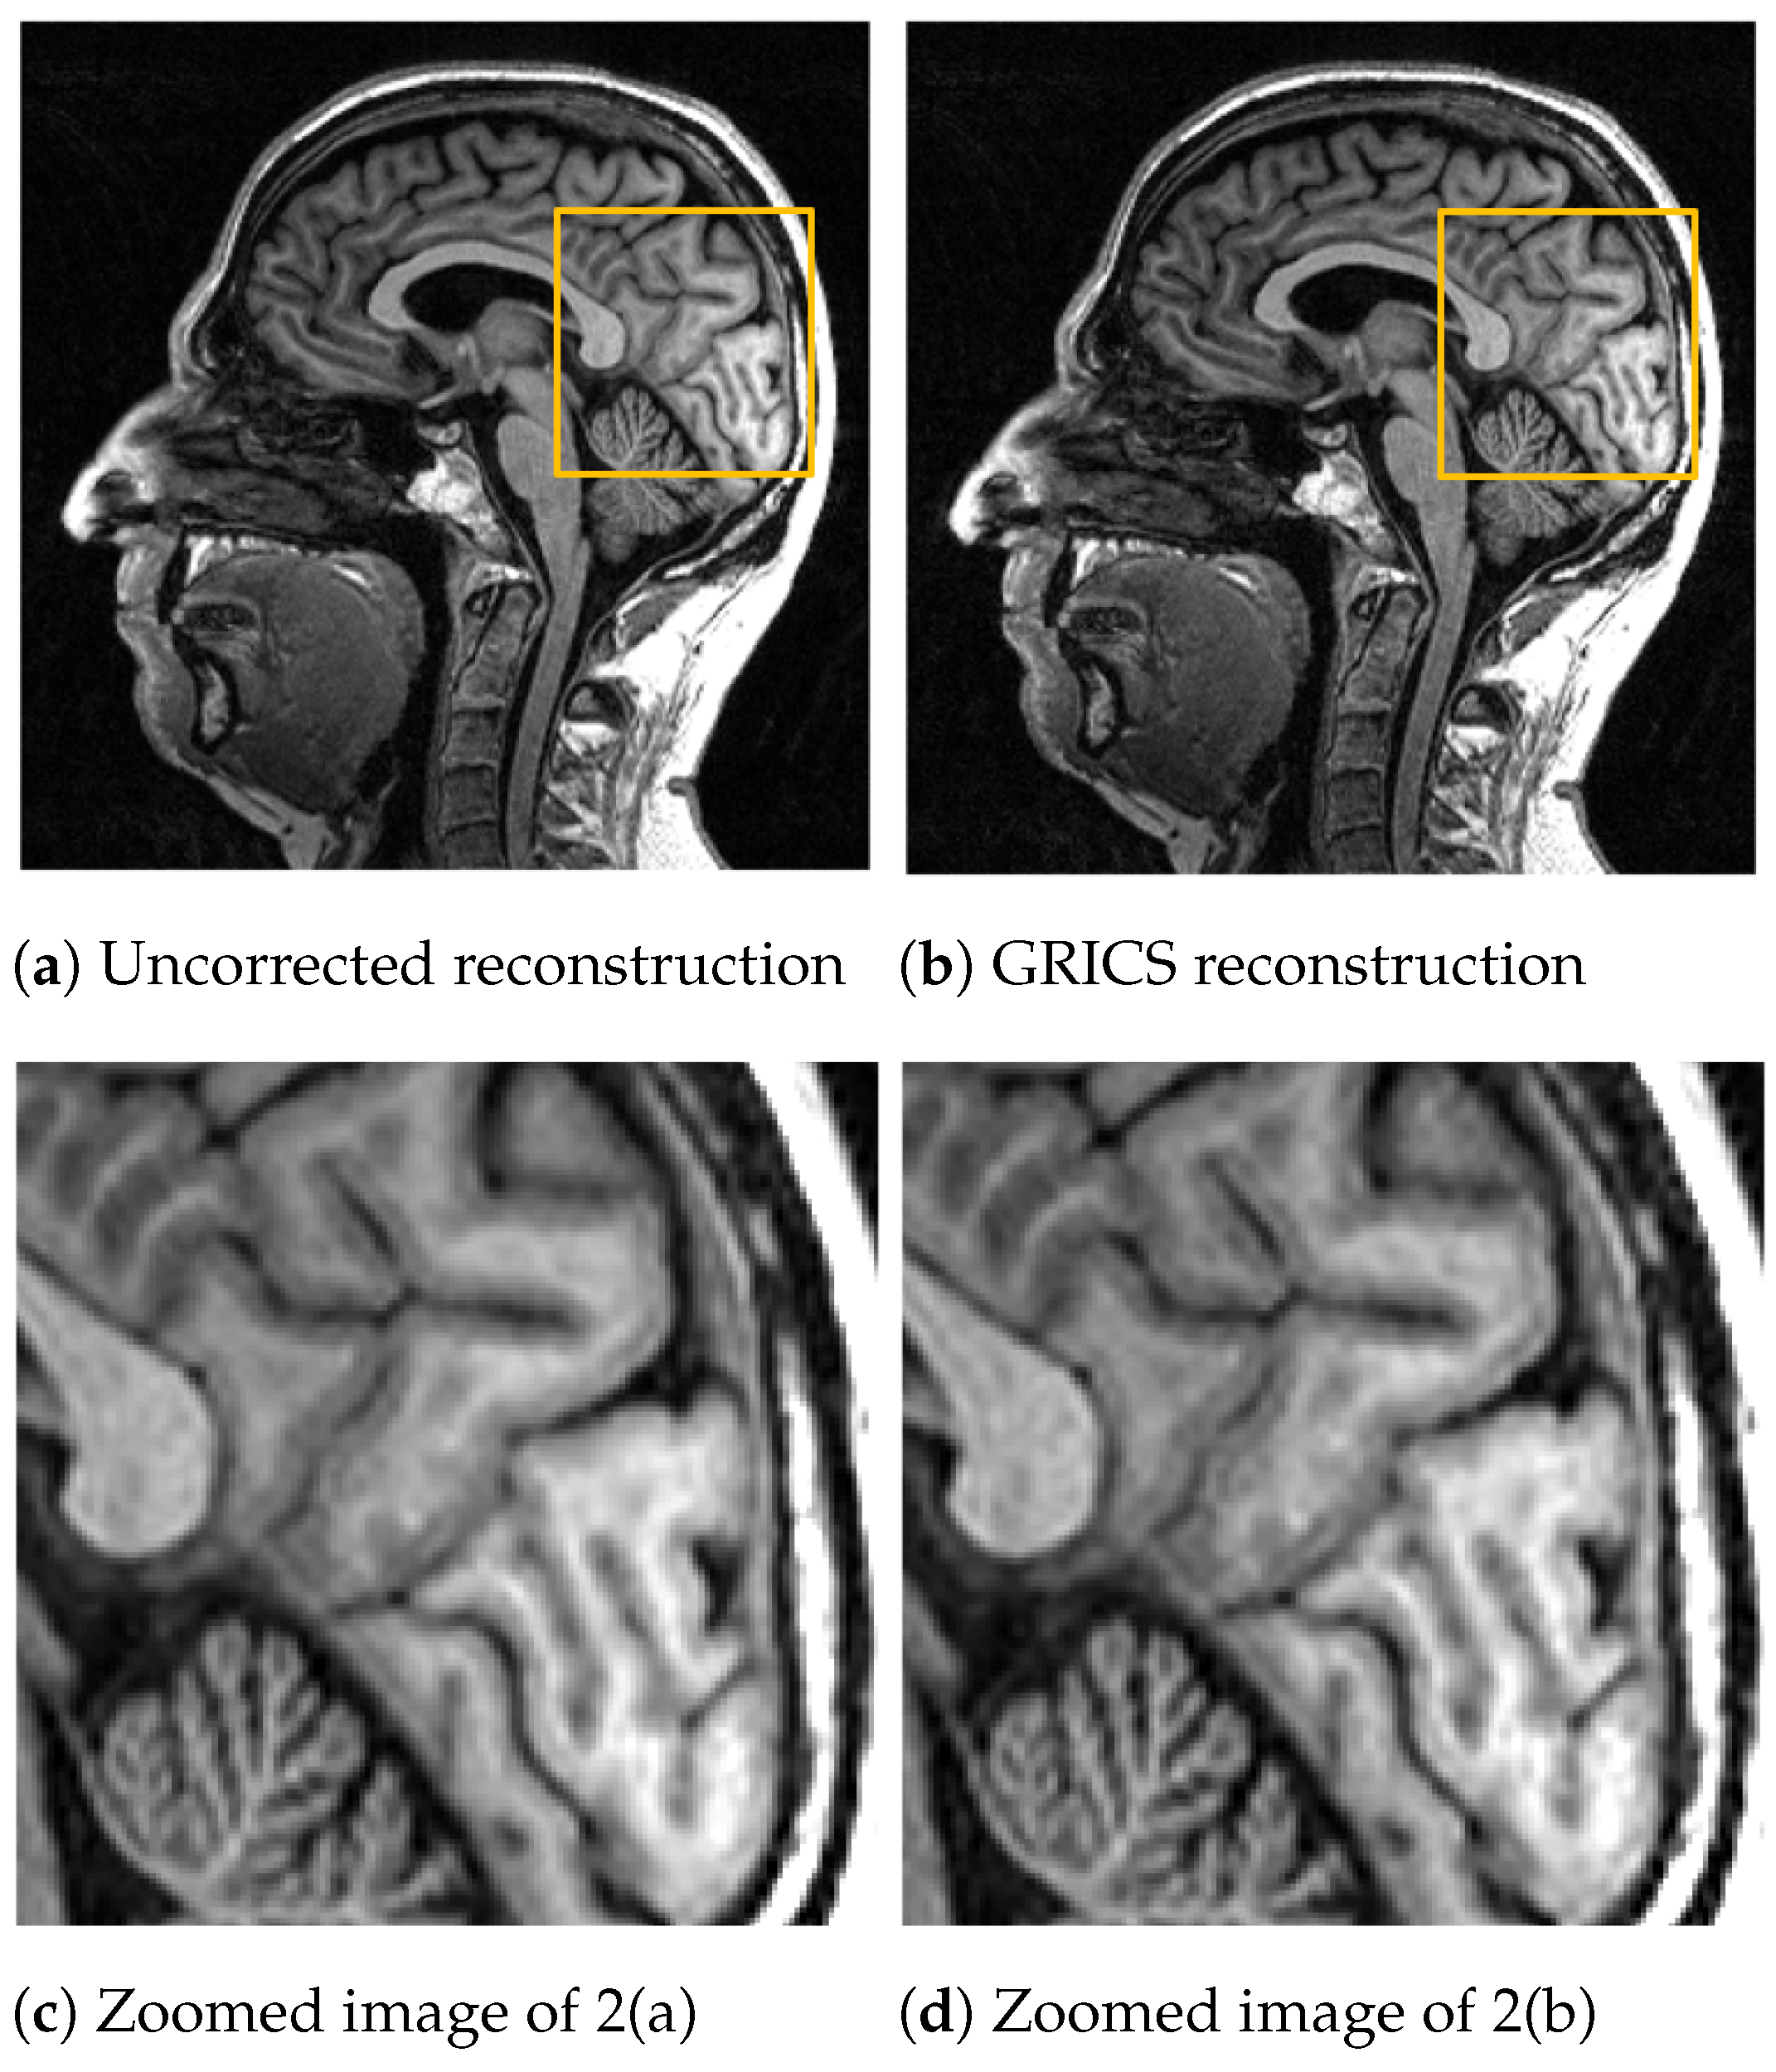

For the generalized reconstruction problem, we set . For the model optimization, we choose . The coil sensitivity maps are computed from the central lines of k-space data with 24 calibration lines and smoothed with second-order splines with a smoothing factor for both magnitude and phase. Examples of GRICS reconstruction are presented in Figure 1 and Figure 2. Figure 1 illustrates a non-rigid motion-compensated breast MRI reconstruction, where we can see an improvement in the reconstruction quality compared to the uncorrected reconstruction. Figure 2 demonstrates a rigid motion-compensated brain MRI reconstruction. The patient was instructed not to move; hence, there was no significant difference between the uncorrected and motion-corrected images. The overall maximum amplitude of motion was: 1.55 degrees for rotation and 0.7 mm for translation, indicating that the motion was minimal.

Figure 2.

Comparison between a reconstruction without motion correction and GRICS reconstruction. Sixteen motion states were considered, dataset . This MRI acquisition was conducted without obvious motion. For quantitative comparison, we determined the sharpness index [] of the images. The index was equal to for the uncorrected reconstruction and for the corrected reconstruction.